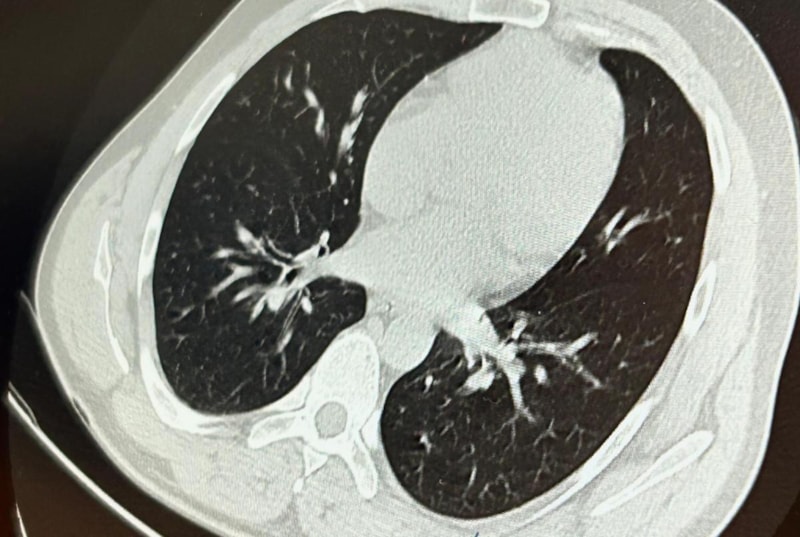

SOL AKCİĞERİN ÜST LOBUNA SAPLANDIĞI TESPİT EDİLDİ

Sol akciğerin üst lobunda saplanmış şekilde tespit edilen vida, vidalı yapısı ve bulunduğu konum nedeniyle güçlükle yerinden oynatılabildi.

İlk olarak hastanenin ek hizmet binasında çekilen tomografi sonucunda, vidanın sol akciğerin hava yollarının yaklaşık dördüncü dalına kadar ilerlediği tespit edildiğini ifade eden Op. Dr. Aksoy, şunları kaydetti:

Aynı gün hastamızı hazırladık. Bronkoskopi sırasında, implant vidasının sol üst lobun anterior segment bronşuna saplanmış pozisyonda olduğunu gördük. Üroloji bölümünde taş çıkarma işlemlerinde kullanılan cihazla müdahale ettik.